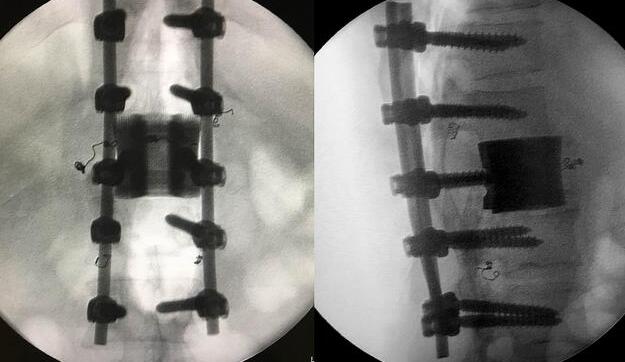

增材制造的椎體/腰間盤一體化植入物

為了更好的完成手術,陳建庭主任、鄭明輝副主任醫師等骨科專家與華鈦三維的3D打印團隊從2017年10月份開始籌備該手術??紤]到每一個病人的脊椎形狀都存在差異,骨科專家認為用一個現成的標準植入物不大可能匹配病人的生理參數。醫生和工程師們根據病人脊柱的CT掃描數據,為病人的脊柱建立了精準的3D圖像。根據這個圖像,治療團隊就能夠設計并定制出屬于病人的個性化植入物。為了使個性化定制的人工椎體與病人椎體之間更好的融合,手術實施前治療團隊先后設計了100多個方案,制作了數十個植入物的術前模型進行研討。事實證明,手術***終使用的植入物是***適合手術和病人身體情況的。

鄭明輝醫生表示,該3D打印人工椎體特殊之處在于其海綿狀的微孔結構結合拓撲框架結構。這種內嵌拓撲框架金屬骨小梁,既有利于相鄰正常脊椎的骨細胞長入其中,***終實現骨融合,又保證了椎體的整體力學性能。

利用3D打印技術生產出來的人工椎體是完全按照患者的解剖結構完成脊椎結構重建及固定的, 裝上一枚精準的、個性化的人工脊椎,患者康復后完全可以正常地生活和工作。過去這種手術常常是使用鈦網內填入自體或異體碎骨作為椎體間支撐材料,但鈦網一旦移位壓迫脊髓,患者就會有癱瘓的風險。這次手術中的脊椎植入物內部具有經過力學優化設計的晶格結構,比傳統鈦網具有更強的承重力,金屬3D打印可以直接制造出這樣的復雜結構。

***終在經歷近八個小時后,病人的家屬終于等到了好消息:人工椎體/椎間盤一體化金屬植入物成功植入,手術順利。由于病人術中出血量小,生命體征平穩,他不用進入ICU觀察,直接回到了普通病房。 現在我們都很高興,成功做出了世界首例人工椎體/椎間盤一體化金屬植入物,病人今后可以與常人一樣工作和生活。鄭明輝醫生說。